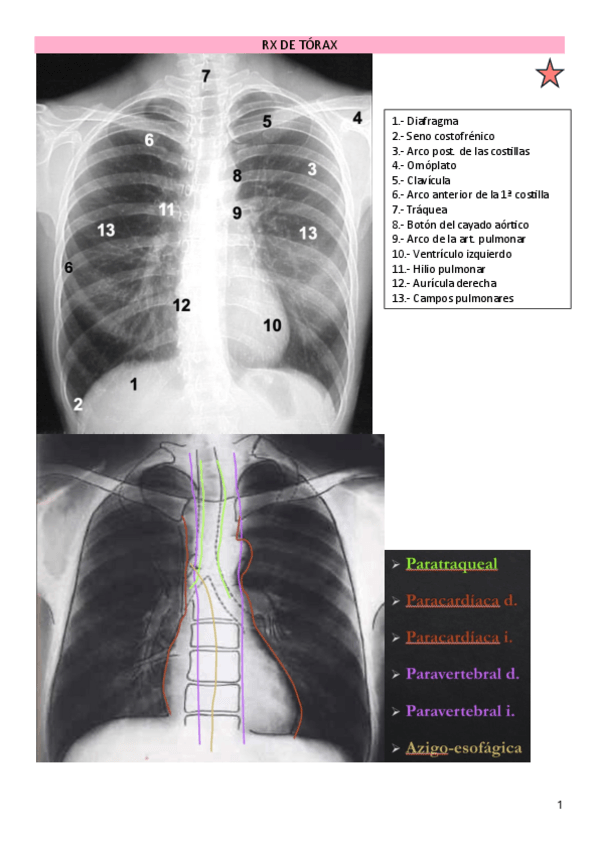

PRÁCTICAS RAYOS X 2023